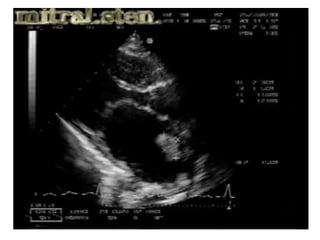

Parachute Mitral valve

• 49.

• 52.

• 54.